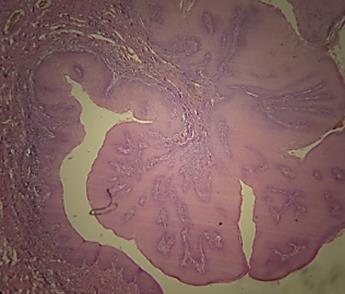

Se tomó biopsia incisional donde se observóepitelioescamosoestratificadoque se continua con masas células neoplásica conpleomorfismocelularynuclear,pérdida de la relación núcleo citoplasma, mitosis aberrantes y aumentadas, nucleolos evidentes y queratinización individual y grupal que infiltraban tejido conjuntivo subyacente; (Fig. 12) por lo que se diagnósticacomoCarcinomaoraldecélulas escamosas, Se realizo PCR al bloque de parafinapor indicación deloncólogodonde fuepositivoalVPH52,porloqueseindicó inmunoterapianeoadyuvante

Fig. 12

Carcinoma oral de células escamosas, vista microscópica, tinción hematoxilina y eosina, autoría propia.

Nota:Fototomadaporelautor